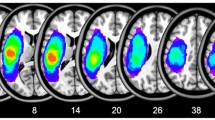

Aphasia types were classified based on the Western Aphasia Battery-Revised (WAB-R) (Kertesz 2007), which was administered by licensed speech-language pathologists (for full details of data fidelity and quality control, see (Spell et al. 2020)). Among the 96 participants included in the study sample, 39 were diagnosed with anomic aphasia, and 57 were diagnosed with Broca’s aphasia. Figure 1 shows a lesion overlap map of the participants in the two groups. Demographic statistics of the two groups are summarized in Table 1. The mean age in the anomic group was 62.73 y.o. (s.d. \(=11.97\); range \(=41\)) and the mean age in the Broca’s group is 59.82 y.o. (s.d. \(=10.35\); range \(=39\)). Respectively \(60\%\) and \(68\%\) of the participants in the anomic and Broca’s group were male. There was no significant difference in age and gender between the anomic and Broca’s group (age: p-value \(=0.42\) by two-sample t-test; gender: \(p =0.74\) by \(\chi ^2\)-test). All participants were in the chronic (>6 months) stage of stroke, where brain and behavior are more stable than in the initial months following stroke (acute stage) (Maas et al. 2012). For the anomic group, time post-stroke was a mean of 2.9 y (s.d. \(=3.42\); range \(=15\)) and for Broca’s was 4.3 y (s.d. \(=4.29\); range \(=16.5\)). This difference was not significant (\(p >.1\)). The mean WAB-R score for the anomic group was 85.74 (s.d. \(=6.38\); range \(=22.1\)) and 46.44 (s.d. \(=16.93\); range \(=59.1\)) for the Broca’s group. As shown in Fig. 2, the WAB-R score for the anomic group is significantly higher than the Broca’s group (p-value \(<0.01\) by two-sample t-test), since the participants with Broca’s aphasia tend to have a lower score in the section of fluency and repetition than the participants with anomic aphasia.